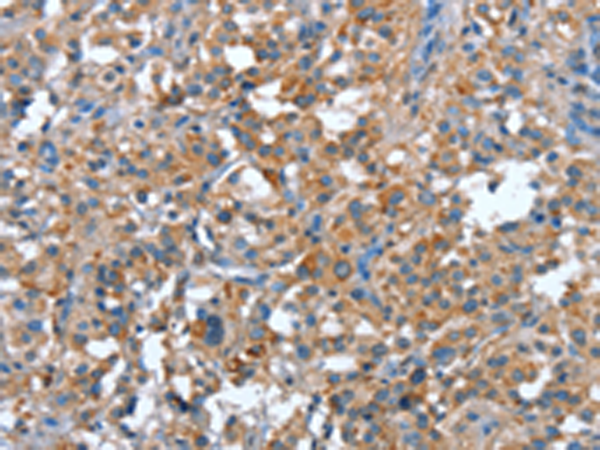

分类: 科研抗体货号: P04734别名: GVI; PLA2; INAD1; NBIA2; iPLA2; NBIA2A; NBIA2B; PARK14; PNPLA9; CaI-PLA2; IPLA2-VIA; iPLA2beta应用: IHC反应种属: Human, Mouse, Rat